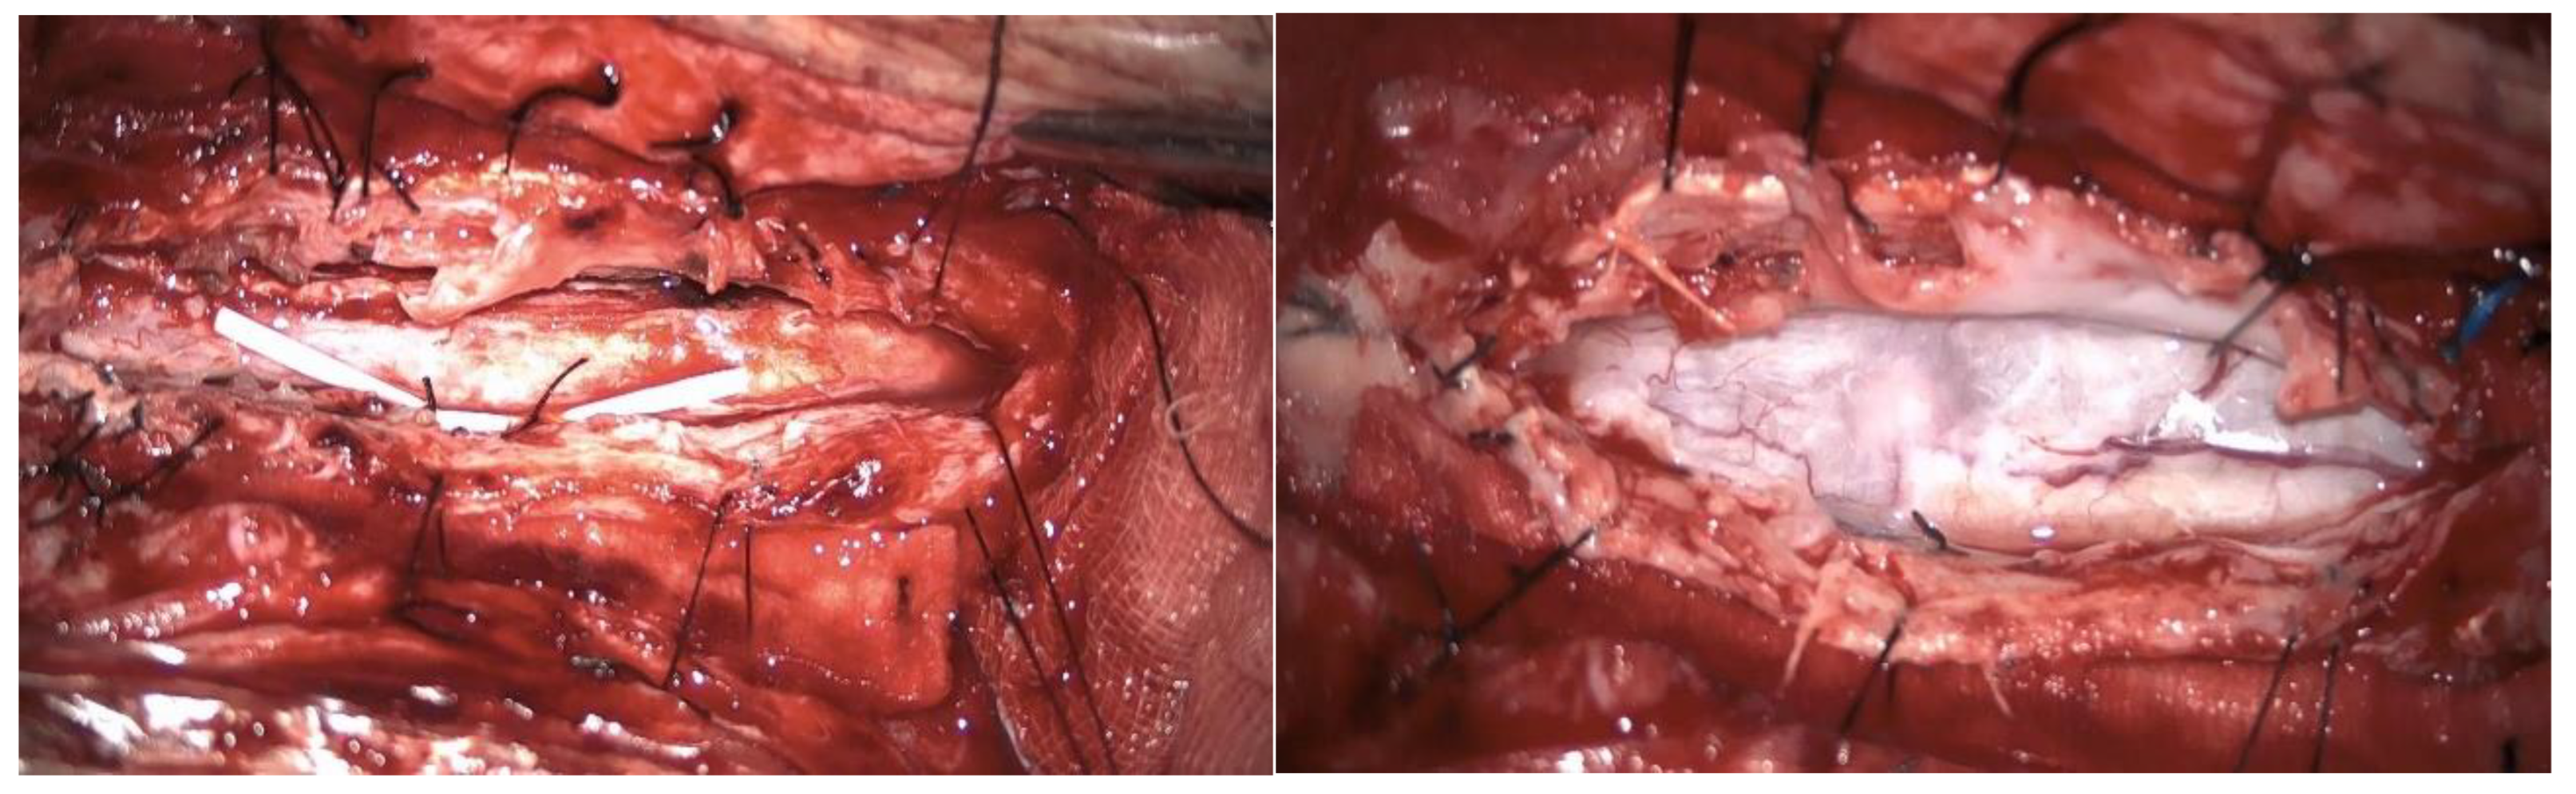

Figure 7. Case 4: syringoperitoneal shunt placement and adhesion lysis.

A second surgery addressed the syringomyelia with laminectomy (D7-D10) and adhesion lysis: postoperative MRI showed resolution of the cyst but persistent malacic changes. A cerebrospinal fluid fistula was treated surgically. After further deterioration and expansion of the syringomyelic cavity, a third surgery including reopening of the previous surgical incision and exposure of the laminectomy allowed the dissection of numerous scar septa both above and below the dural plane, freeing the spinal cord circumferentially. A myelotomy was performed to drain the syringomyelic cavity and establish communication with the subdural space, placing of a syringoperitoneal shunt and additional adhesion lysis [Figure 7]. Post-operative MRI indicated reduced syringomyelic size [Figure 8]. The patient remains clinically stable after 4 years of follow-up.